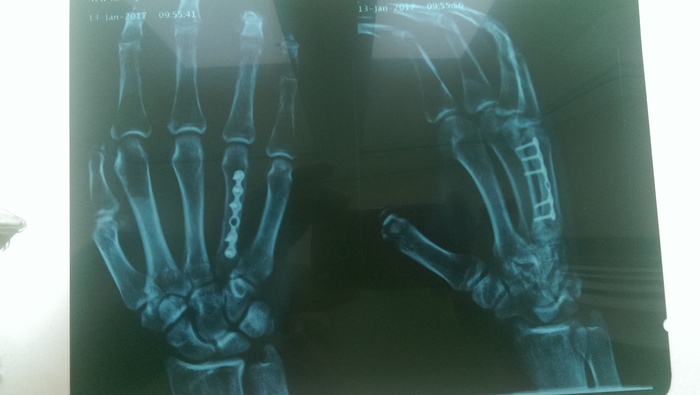

вот он, переломчик

а так теперь выглядит рука на рентгене